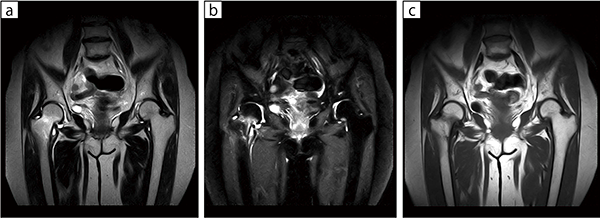

■症例2:大腿骨頸部骨折

一般撮影では骨折による転位がほとんどなく骨折がわかりにくかったが,T2強調画像(a)と脂肪抑制画像(b)で大腿骨の頸部が高信号を示しており,頸部骨折と診断できる。

a:RADAR-T2WI,COR,FOV:340mm,TR/TE=3378/112,スライス厚:5mm

b:STIR,COR,FOV:340mm,TR/TE/TI=3800/17/110,スライス厚:5mm

c:T1WI,COR,FOV:340mm,TR/TE=400/25,スライス厚:5mm